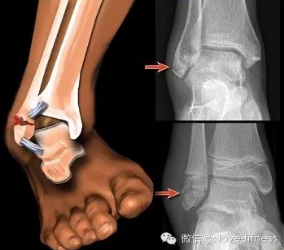

轻度崴脚只是软组织的损伤,稍重的就可能是外踝或者第五跖骨基底骨折,再重的还可能是内、外踝的双踝骨折,甚至造成三踝骨折。轻的可以自己处置,重的就必须到医院请医生诊断和治疗。所以,分辨伤势的轻重非常重要。

如果自己活动足踝时有剧痛,不能持重站立和挪步,疼的地方在骨头上,或扭伤时感觉脚里面发出声音,伤后迅速出现肿胀,尤其是压痛点在外踝或外脚面中间高突的骨头上,那是伤重的表现,应马上到医院去诊治。